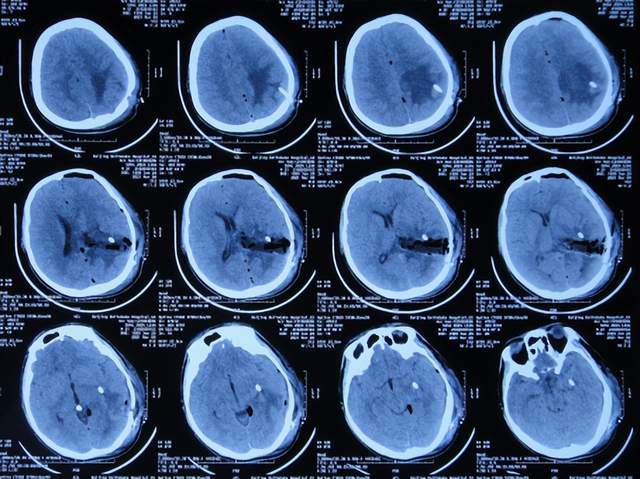

2021年2月5日(脑膜瘤切除术后颅内感染3周)住入李小勇脑脊液科,入院时:精神差,食欲差,体温高(图-13);查头颅CT示脑瘤术后状态(图-14);(外院)2021年2月3日头颅核磁示有脑脓肿(图-12)。

图-13:2021年2月5日入院时

图-14:2021年2月5日头颅CT

入院后3天即2021年2月8日,左颞角脑室腹壁外引流术(图-15)。

图-15:2021年2月8日头颅CT

左颞角脑室腹壁外引流术后8天即2021年2月16日,查头颅CT示颞角缩小(图-16)。

图-16:2021年2月16日头颅CT

左颞角脑室腹壁外引流术后21天即2021年3月1日,查头颅CT示颞角仍有扩张(图-17)。

图-17:2021年3月1日头颅CT

左颞角脑室腹壁外引流术后23天即2021年3月3日,头颅CT增强和核磁增强示有脑脓肿(图-18、图-19)。

图-18:2021年3月3日头颅CT增强

图-19:2021年3月3日头颅核磁增强

2021年3月8日(左颞角脑室腹壁外引流术后28天),进行了脑脓肿切除术(图-20)。

图-20:2021年3月8日头颅CT

2021年3月9日(左颞角脑室腹壁外引流术后29天,脑脓肿切除术后次日),查头颅CT示脑脓肿切除术后(图-21)。

图-21:2021年3月9日头颅CT

2021年3月11日(左颞角脑室腹壁外引流术后31天,脑脓肿切除术后4天),患者身体状态良好,体温变正常(图-22)。

图-22:2021年3月11日

2021年3月12日(左颞角脑室腹壁外引流术后32天,脑脓肿切除术后5天),查头颅CT示仍有少量水肿(图-23)。

图-23:2021年3月12日头颅CT

2021年3月26日(左颞角脑室腹壁外引流术后46天,脑脓肿切除术后19天),夹闭引流管1周左右,颞角没有扩张,因此进行了脑室腹壁外引流管拔除术。

但拔除引流管后11天即2021年4月6日,患者出现头痛,查头颅CT示颞角扩张(图-24)。

图-24:2021年4月6日头颅CT

因此于2021年4月8日,进行了脑室腹腔分流术;术后身体一切正常(图-25)。

图-25:2021年4月9日

于2021年4月18日(治疗近3个月)出院,出院时:身体一切正常。